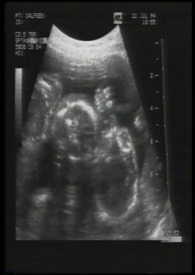

我们总期待着新生命的降临,但却从不知道那来到身旁的,表象为人类的肉块容器中,真的是装着我们所期待的未来吗?我们是否有权利决定或主导它的一切?那是一栋被搁置许久的空屋,听房子拥有者是这么